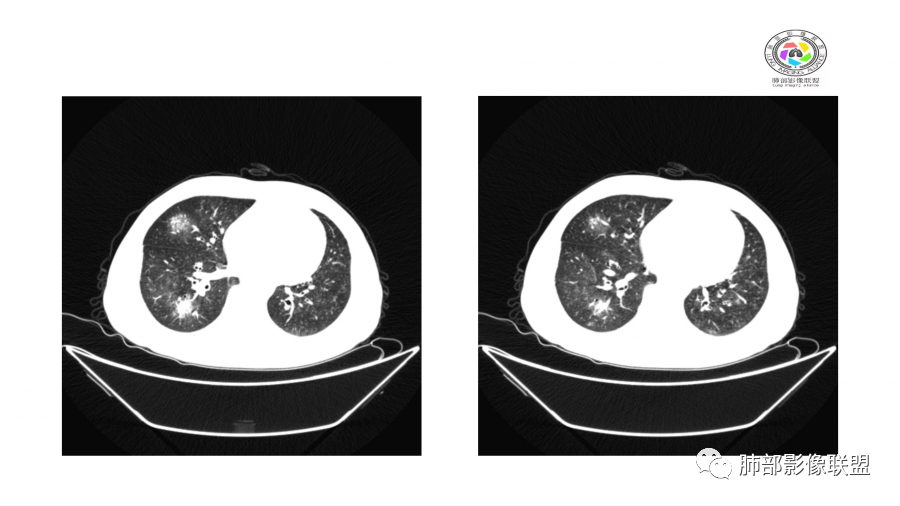

中年男性,高血压,肾功能衰竭,贫血病史,尿潜血阳性。3.8双肺野多发斑片磨玻璃实变影,结节影,边缘模糊,周围有晕征,内见支气管充气征,主要沿支气管血管束分布,部分胸膜下分布,3.12号病灶有吸收好转,4.8号斑片实变影基本吸收,主要沿支气管血管束分布结节影,边缘平直收缩,4.28病灶大部分吸收好转,双肺支气管血管束增粗,有少量结节影。考虑ANCA相关性血管炎可能性大,第一次片子觉得隐球菌不排除,但是后面没有抗真菌治疗就吸收了,觉得隐球菌可能性不大。

胸部CT:双肺多发实性斑片影,散在GGO。实性斑片周围可见晕征、边缘模糊不清,病灶于肺外围区域优势分布。肺门区血管影增粗,支气管套袖,目测肺动脉增粗。3月、4月复查肺内实性斑片病灶呈游走性,此起彼伏。

10天后:病灶继续吸收好转

伴随少量胸水

应该与气道无关

符合间质、血管来源病变

此起彼伏

有肾功能不全

支持与肾病相关

警惕血管炎